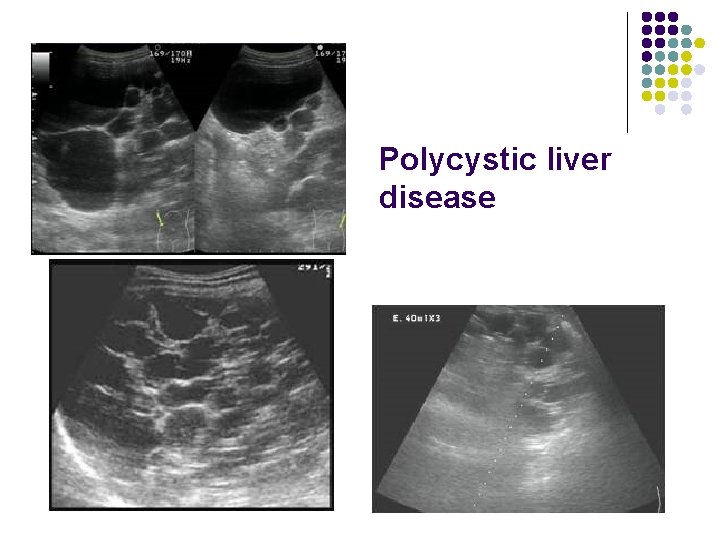

Polycystic liver disease